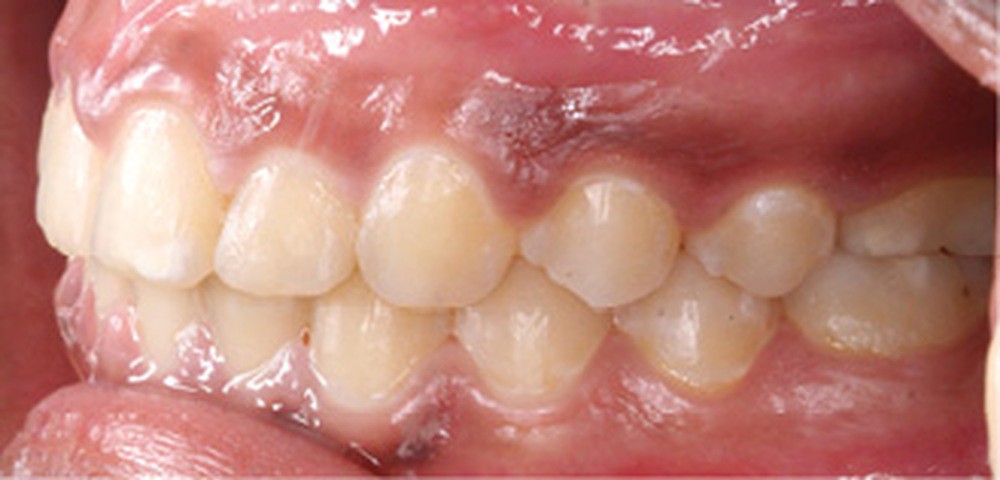

L’arcade maxillaire est en V et la voûte palatine profonde. L’arcade mandibulaire a une forme en U (non-concordance des formes d’arcade) et présente des malpositions des dents cuspidées. La médiane mandibulaire est décalée à gauche de 2 mm ; le recouvrement antérieur est de 2 mm ; les molaires sont en classe III avec un surplomb inversé.

Lors de la réévaluation post-chirurgicale, l’examen exo-buccal montre peu de changement, excepté l’occlusion et l’harmonie labiales retrouvées. Le surplomb et le recouvrement sont normalisés et le brossage amélioré. Les formes d’arcade sont concordantes, les médianes inter-incisives recentrées et les molaires et canines en classe I.